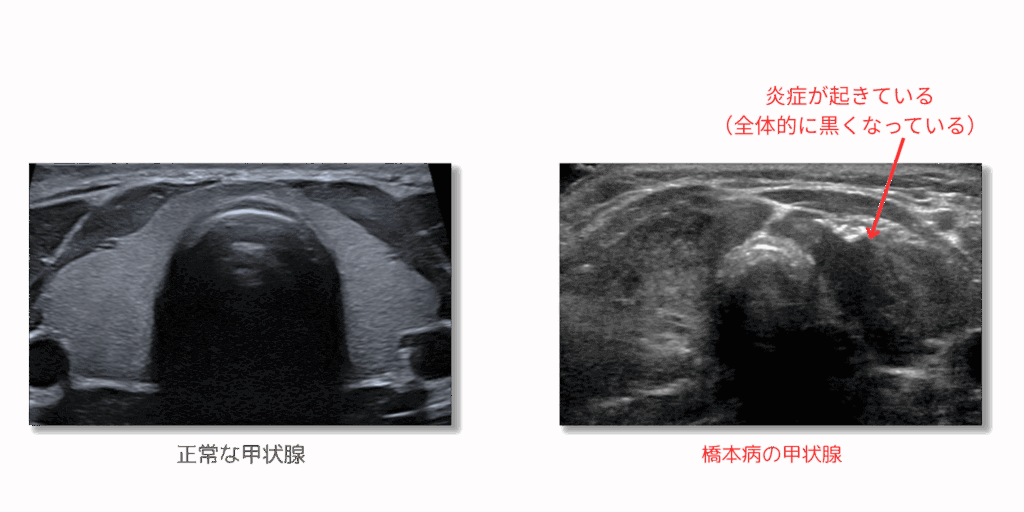

橋本病(慢性甲状腺炎)ドック

橋本病(慢性甲状腺炎)は女性の30人に1人程度の割合で発症すると言われています。「なぜか体調が優れない」「なんとなく体調がおかしい」というような症状が出る病気です。しかし、症状がないまま進行し、遺伝性も関連している可能性がある病気です。親族で甲状腺に異常を指摘された方がいらっしゃる場合は特にご検討ください。

また、甲状腺は腫瘍が比較的できやすい臓器でもあり、甲状腺がんを疑うような腫瘍ができていないかも同時に評価します。

| 検査の種類 | 検査内容 | ||

| 理学的検査 | 問診(既往歴・業務歴)、医師診察 | ||

| 血液検査 | FT3、FT4、TSH、サイログロブリン、抗サイログロブリン抗体、抗TPO抗体 | ||

| 画像検査 | 甲状腺エコー |